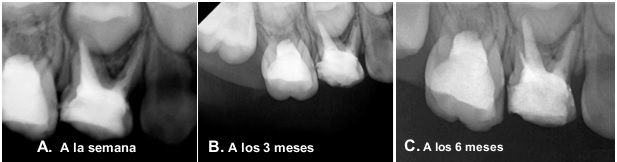

Una semana después, en la cita de control, la paciente no presentó dolor a la percusión vertical durante el examen clínico. Asimismo, se identificó movilidad dentaria de grado 1, determinada mediante presión en sentido vestíbulo-palatino con dos instrumentos metálicos. Radiográficamente, se observó una IRO intraconducto compatible con la obturación de los conductos radiculares, así como una IRL a nivel interradicular con pérdida de la lámina dura y ensanchamiento del espacio del ligamento periodontal en la superficie distal de la raíz mesiovestibular (figura 4A).

Tres meses después, la paciente mostró las mismas características clínicas y radiográficas (figura 4B). A los seis meses, no presentó molestias, dolor ni movilidad dental, y no se evidenciaron manifestaciones clínicas de procesos infecciosos de origen dentario. Radiográficamente, se observó una disminución del ensanchamiento del espacio del ligamento periodontal en la superficie distal de la raíz mesiovestibular, así como la ausencia de IRL a nivel interradicular, lo que indica la reparación de la lámina dura (figura 4C).

Figura 4. Controles radiográficos después del retiro del instrumento. A y B) A la semana y a los 3 meses: imagen radiolúcida a nivel interradicular con pérdida de lámina dura. Ensanchamiento del espacio para el ligamento periodontal en superficie distal de raíz mesiovestibular. C) A los 6 meses: disminución del ensanchamiento del espacio para el ligamento periodontal en superficie distal de raíz mesiovestibular, ausencia de imagen radiolúcida a nivel interradicular.